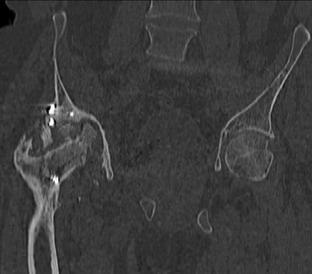

Пациент 49 лет, паровозная травма 23.2.2006, получил вертикальная нестабильное повреждение таза, разрыв левого крестцово-подвздошного сочленения, перелом лонной, седалищной костей слева, T-образный оскольчатый перелом правой вертлужной впадины с переломом заднего края, вывих правого бедра, посттравматическая пояснично-крестцовая плексопатия с обеих сторон, паралич мышц правой голени. В день травмы - вправление вывиха, скелетное вытяжение, 14.3.2006 чрескостный остеосинтез таза. 20.4.2006 остеосинтез правой вертлужной впадины пластинами, осложнившийся нагноением межмышечной гематомы правой ягодичной области. Получал консервативное лечение, было достигнуто полное заживление раны. 24.7.2006 введены илиосакральные винты слева. С декабря 2006 года и по настоящее время ходит на костылях без опоры на правую ногу. Планируется THA. Помогите определиться с вариантом костной пластики? И какую укрепляющую конструкцию использовать?

Мне кажется, будет вполне достаточно кольца Muller, костная пластика из остатков головки чипсами (нужно иметь виду, что собственной головки может не хватить и она может оказаться ненадлежащего качества, поэтому лучше иметь запас аллокости) возможна и структурная пластика, точно алло.

Бесцементная чаша, с восстановлением нормального центра вращения и с костной аутопластикой дна впадины. А Рыков Хабаровск.

Паровозы-элктровозы. Суть не в этом. Сейчас - аутокостная реконструкция вертлужной впадины. Ало - оногда секвестрация. Не надо риска. И, есле готовы технически, эндопротезирование. Лучше бесцесентная чашка прес-фит (допустем - зимет) с дополнительной фиксацией винтами. Возможен вариант кольца Мюллеа. Операцию возможно выполнить в один либо два этапа. Первы -реконструкция вертлужной впадины,а второй - протез через 3-4 мес. Кость лучше брать из гребня, т.к. головка с некрозом-склерозом-фиброзом.